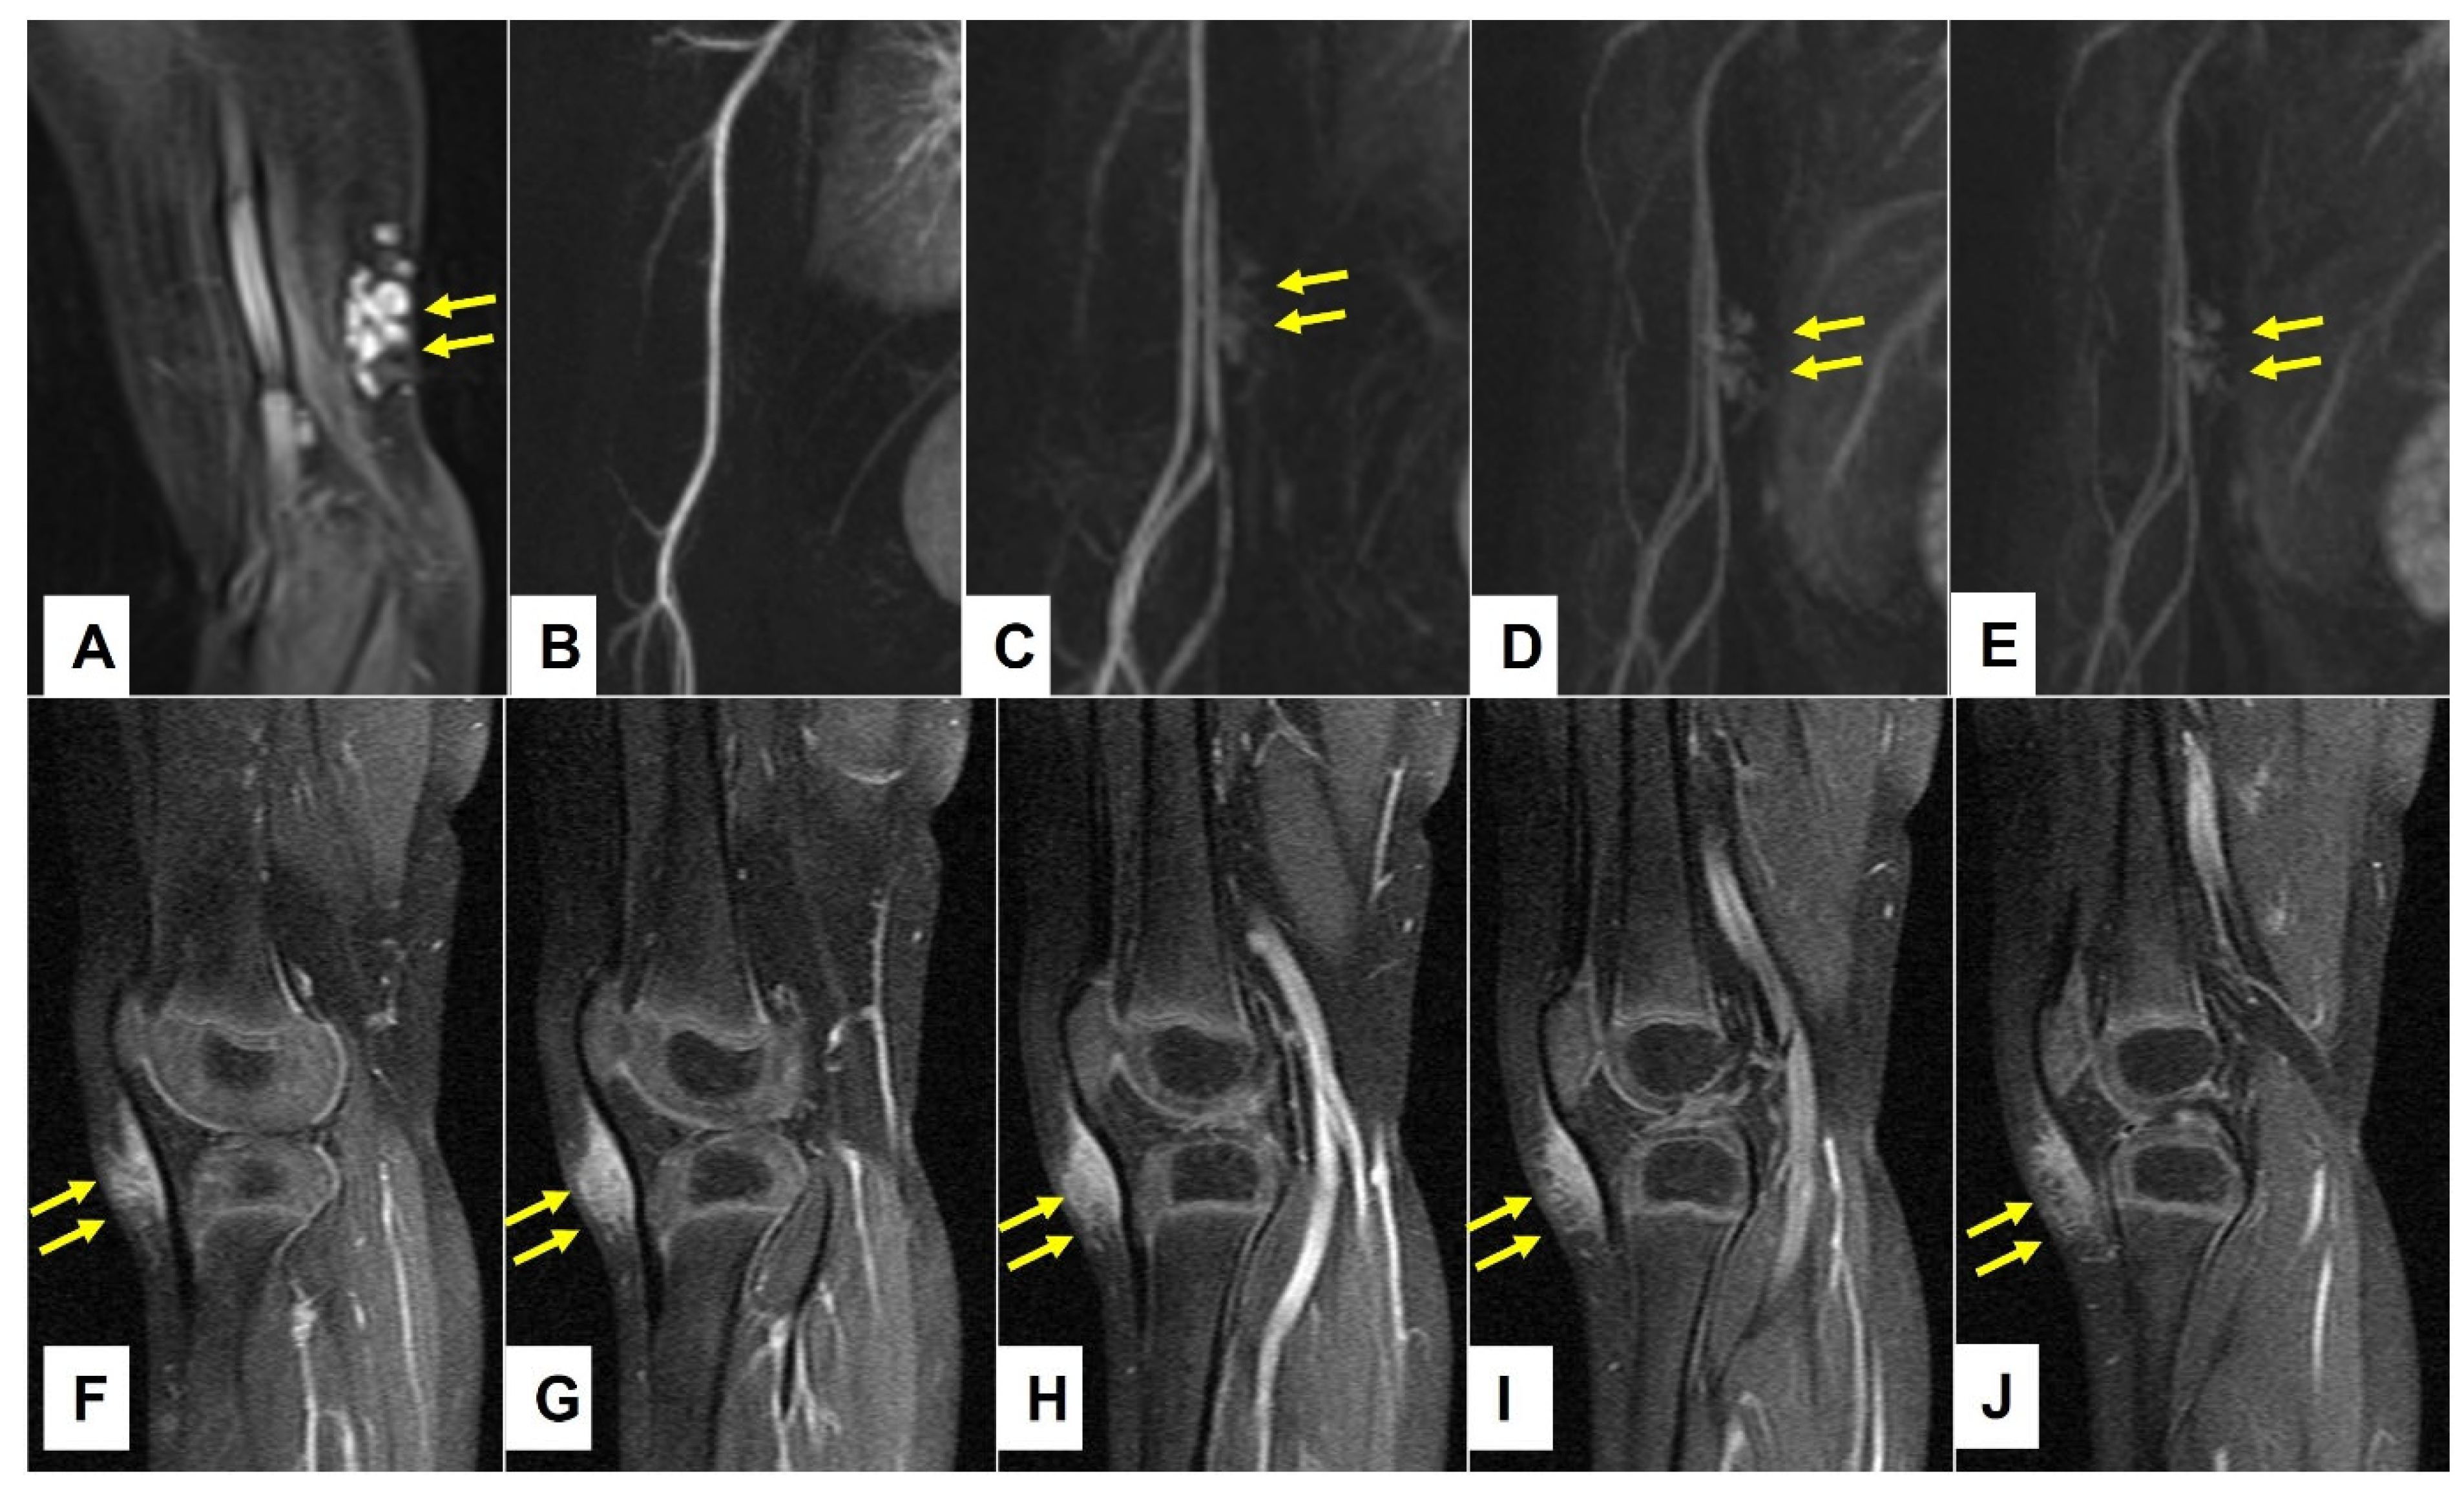

Figure 9.

This composite figure illustrates the typical imaging differences between the low-flow subcutaneous vascular malformations (SVM) and subcutaneous granuloma annulare (SGA) as seen on the MR images. In images (A–D), four patients with multicystic subcutaneous lesions pointed out by yellow arrows are presented. These lesions were accurately diagnosed by MRI and after excision, also confirmed by histopathology as a venous malformation on the left knee in an 11-year-old boy (A); venous malformation on the right upper arm in a 4-year-old boy (B); lymphatic malformation on the right elbow in a 4-year-old girl (C); lymphatic malformation on the left upper arm in an 8-year-old girl (D). In images (E–H), four patients with homogenous subcutaneous lesions marked with 3 yellow arrows each are presented. These lesions remained inconclusive after MRI, with the main differential diagnosis being the low-flow SVM in all cases. Because malignancy could not be excluded, surgical biopsy was needed, and the diagnosis of SGA was confirmed by histopathology in all cases. (E) right knee in a 2.5-year-old boy, (F) right lower leg in a 3-year-old girl, (G) left forearm in a 4-year-old boy, (H) left foot in a 3-year-old girl. Note that all SVM have a cystic appearance on the MRI, whereas SGA shows the typical epifascial extension with gradual rise of the lesion towards the more superficial tissues, which we have named the “epifascial cap” sign. These self-limiting lesions show a homogenous appearance in the MRI and do not invade the fascia.

Figure 10.

These images show representative MRI slices through SGA (indicated by white arrows) at the knee (A); lower leg (B); forearm (C); and foot (D) in four different cases. Note that all SGA lesions show the typical epifascial extension with gradual rise of the lesion towards the more superficial tissues, which we have named the “epifascial cap” sign.

3.3. Retrospective Image Analysis

A retrospective review of all MR images showed that all MRIs of patients with low-flow SVMs showed multicystic and/or tubular lesion appearance, whereas MRIs of patients with SGA never showed any cyst-shaped structures. An SGA presents as a raised-rounded homogenous mass that projects over the surface of the muscle’s fascia without invading the underlying tissue (Figure 9). These lesions have a typical broad circular base laying on the fascia and a raised, continuous, irregular curved surface that extends from the deep fascia towards the more superficial tissues. One can easily describe the shape of an SGA as an island rising from the ocean. We recently named this characteristic shape “the Epifascial Cap,” the hallmark shape of an SGA (Figure 10) []. The enhancement of contrast material seen in these lesions during the MRI is homogenous and should not be mistaken for a low-flow SVM (Figure 11).